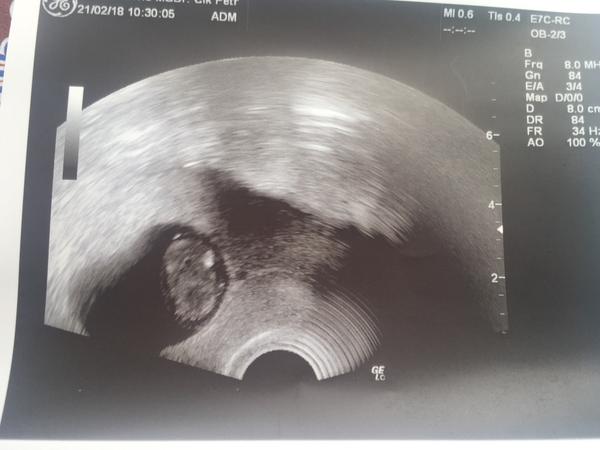

Ahojky tak uz mam po kontrole. Drme zkontroloval a pak oblecte se. Tak sem ho ukecala na utz sice mrmlal ale kdyz sem mu rekla ze minule to ve 13tydnu skoncilo tak pochopil. Zas byl dlouho ticho pak rika mimino tam je ale hledam sedicko a ve me uplne hrklo. Mam to na kazde kontrole ze sou dlouho ticho a pak tady je.... nakonec teda vse ok srdicko bije. Ma prstiky. Vypadalo trochu jak krtek. Na vaginalni utz prej uz je velky a pres bricho je jeste maly. Ale zkusil obe a prcka sem pekne videla. Asi spal pac se nehybal ale srdicko bylo videt tak snad ok. Nemeril ale ptala sem se jestli odpovida velikostne a prej jo. Dalsi kontrola uz u me dr za tri tydny.